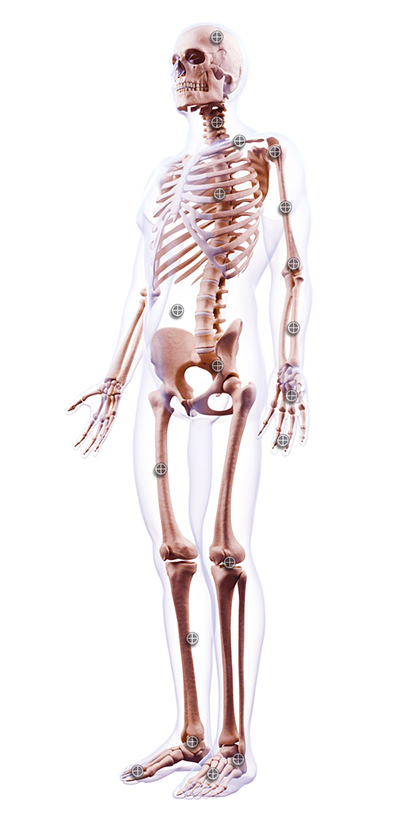

Anatomie

Thoraxbereich

Anatomie Menü

Kopf

Wirbelsäule

Clavicula

Schulter

Oberarm

Ellenbogen

Unterarm

Hand und Handgelenk

Finger

Thorax

Abdomen

Becken / Hüfte

Oberschenkel

Kniegelenk

Unterschenkel

Sprunggelenk

Calcaneus

Fuß

Zehen